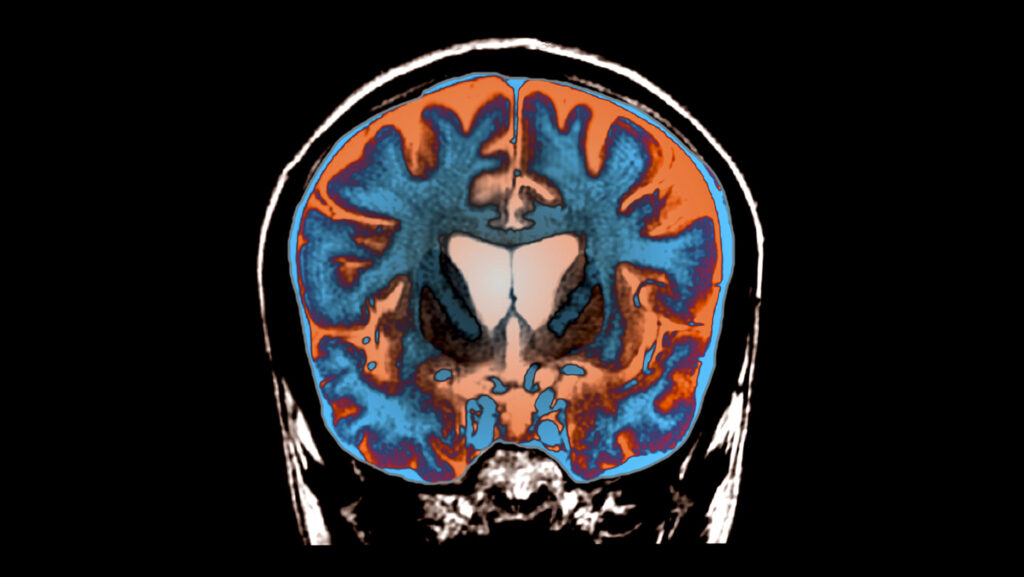

This expanded huntingtin is a protein gone toxic. It aggregates in the brain and kills cells largely in brain areas crucial for voluntary movements. Patients end up with increasing involuntary movements, stiffness, difficulties speaking and swallowing and cognitive decline. Huntington’s is genetically dominant — it takes only one copy of the defective gene to cause it — so a patient’s offspring have a 50 percent chance of inheriting the disease.

In a surgery lasting 12 to 18 hours, 17 patients with early symptoms of Huntington’s disease received injections of viral payload into three spots on each side of the relevant brain areas. The research team then assessed 12 of those patients for 36 months, testing their motor scores, attention, working memory and how well they could go about their daily lives. “It was heroic, really, on behalf of the patients and on behalf of the doctors,” Snell says.